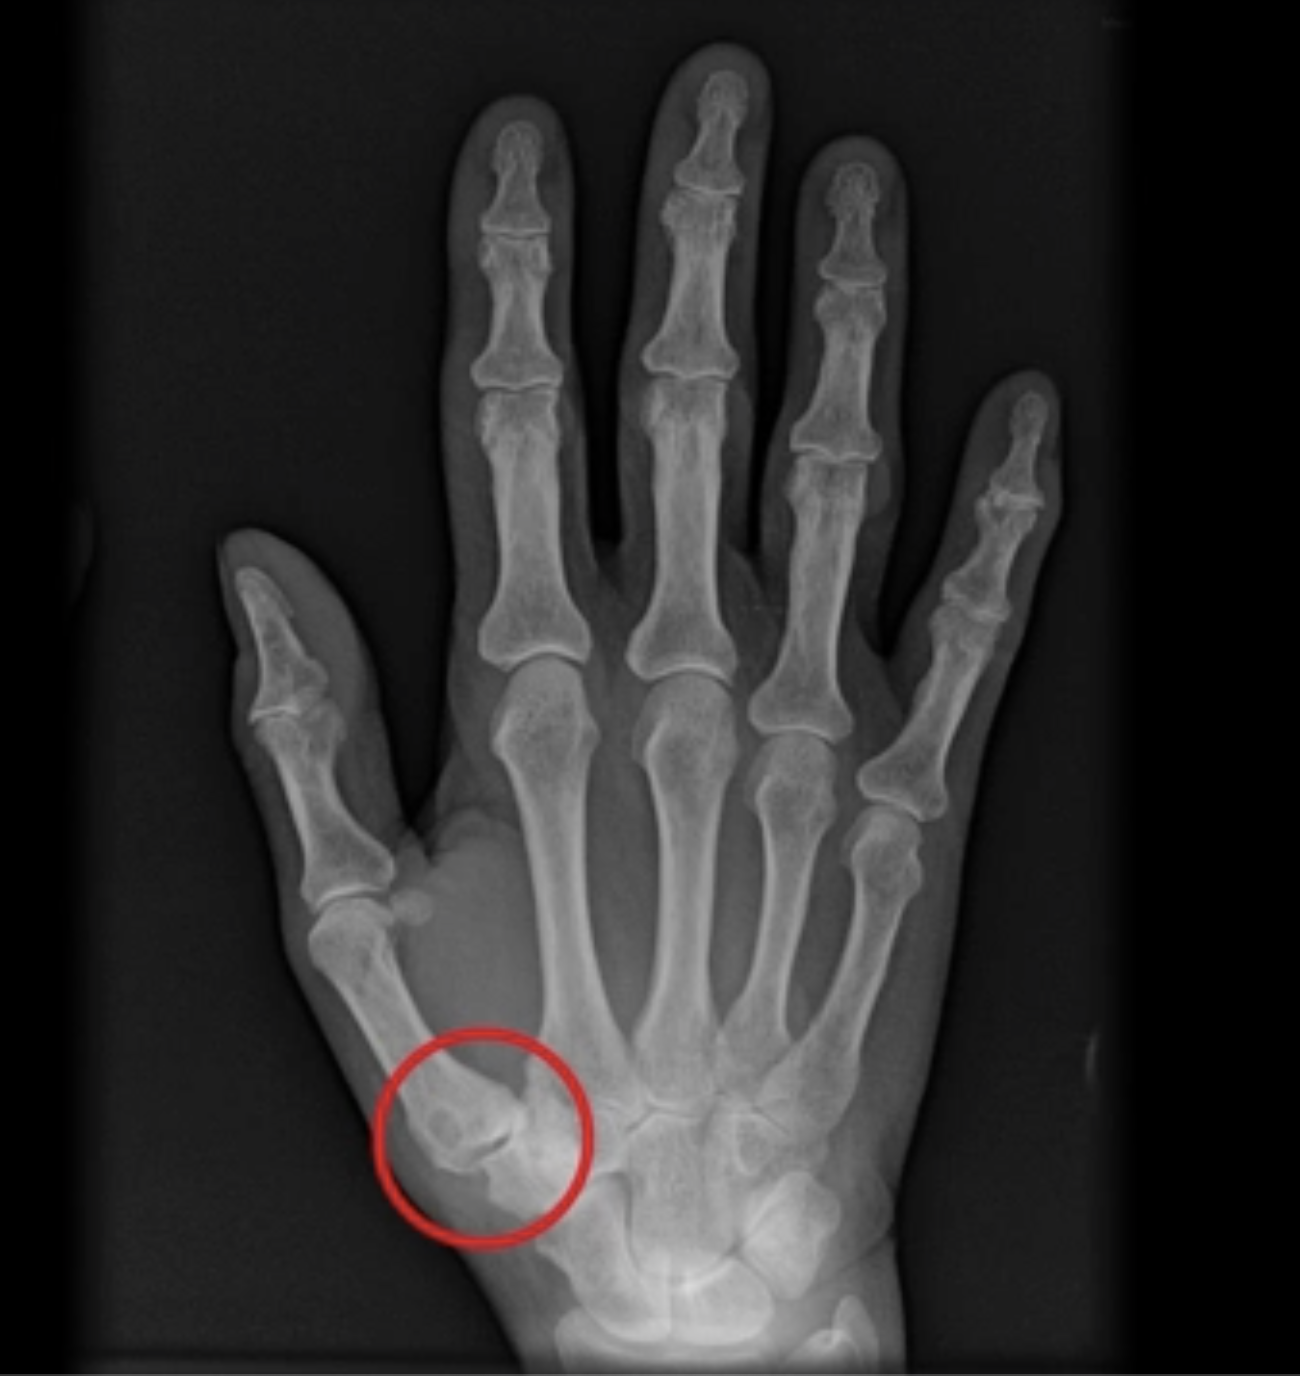

La rizoartrosi è una forma di artrosi che colpisce l'articolazione alla base del pollice, chiamata trapezio-metacarpica. Può essere causata dall'invecchiamento, dallo stress ripetitivo sull'articolazione, da deformità congenite, instabilità, anomalie muscolari o traumi e infiammazioni passate. Questa condizione può portare a perdita di funzionalità del pollice e a deformità visibili.

Figura 1 - Rizoartrosi

La diagnosi di rizoartrosi inizia con una valutazione clinica, confermata poi da esami strumentali (radiografie). Clinicamente si possono rilevare prominenze alla base del pollice e iperestensione dell'articolazione metacarpo-falangea. Test specifici come il grind test e il test di sublussazione possono evocare dolore e rumori articolari caratteristici.

Figura 2 - Radiografia di mano affetta da rizoartrosi